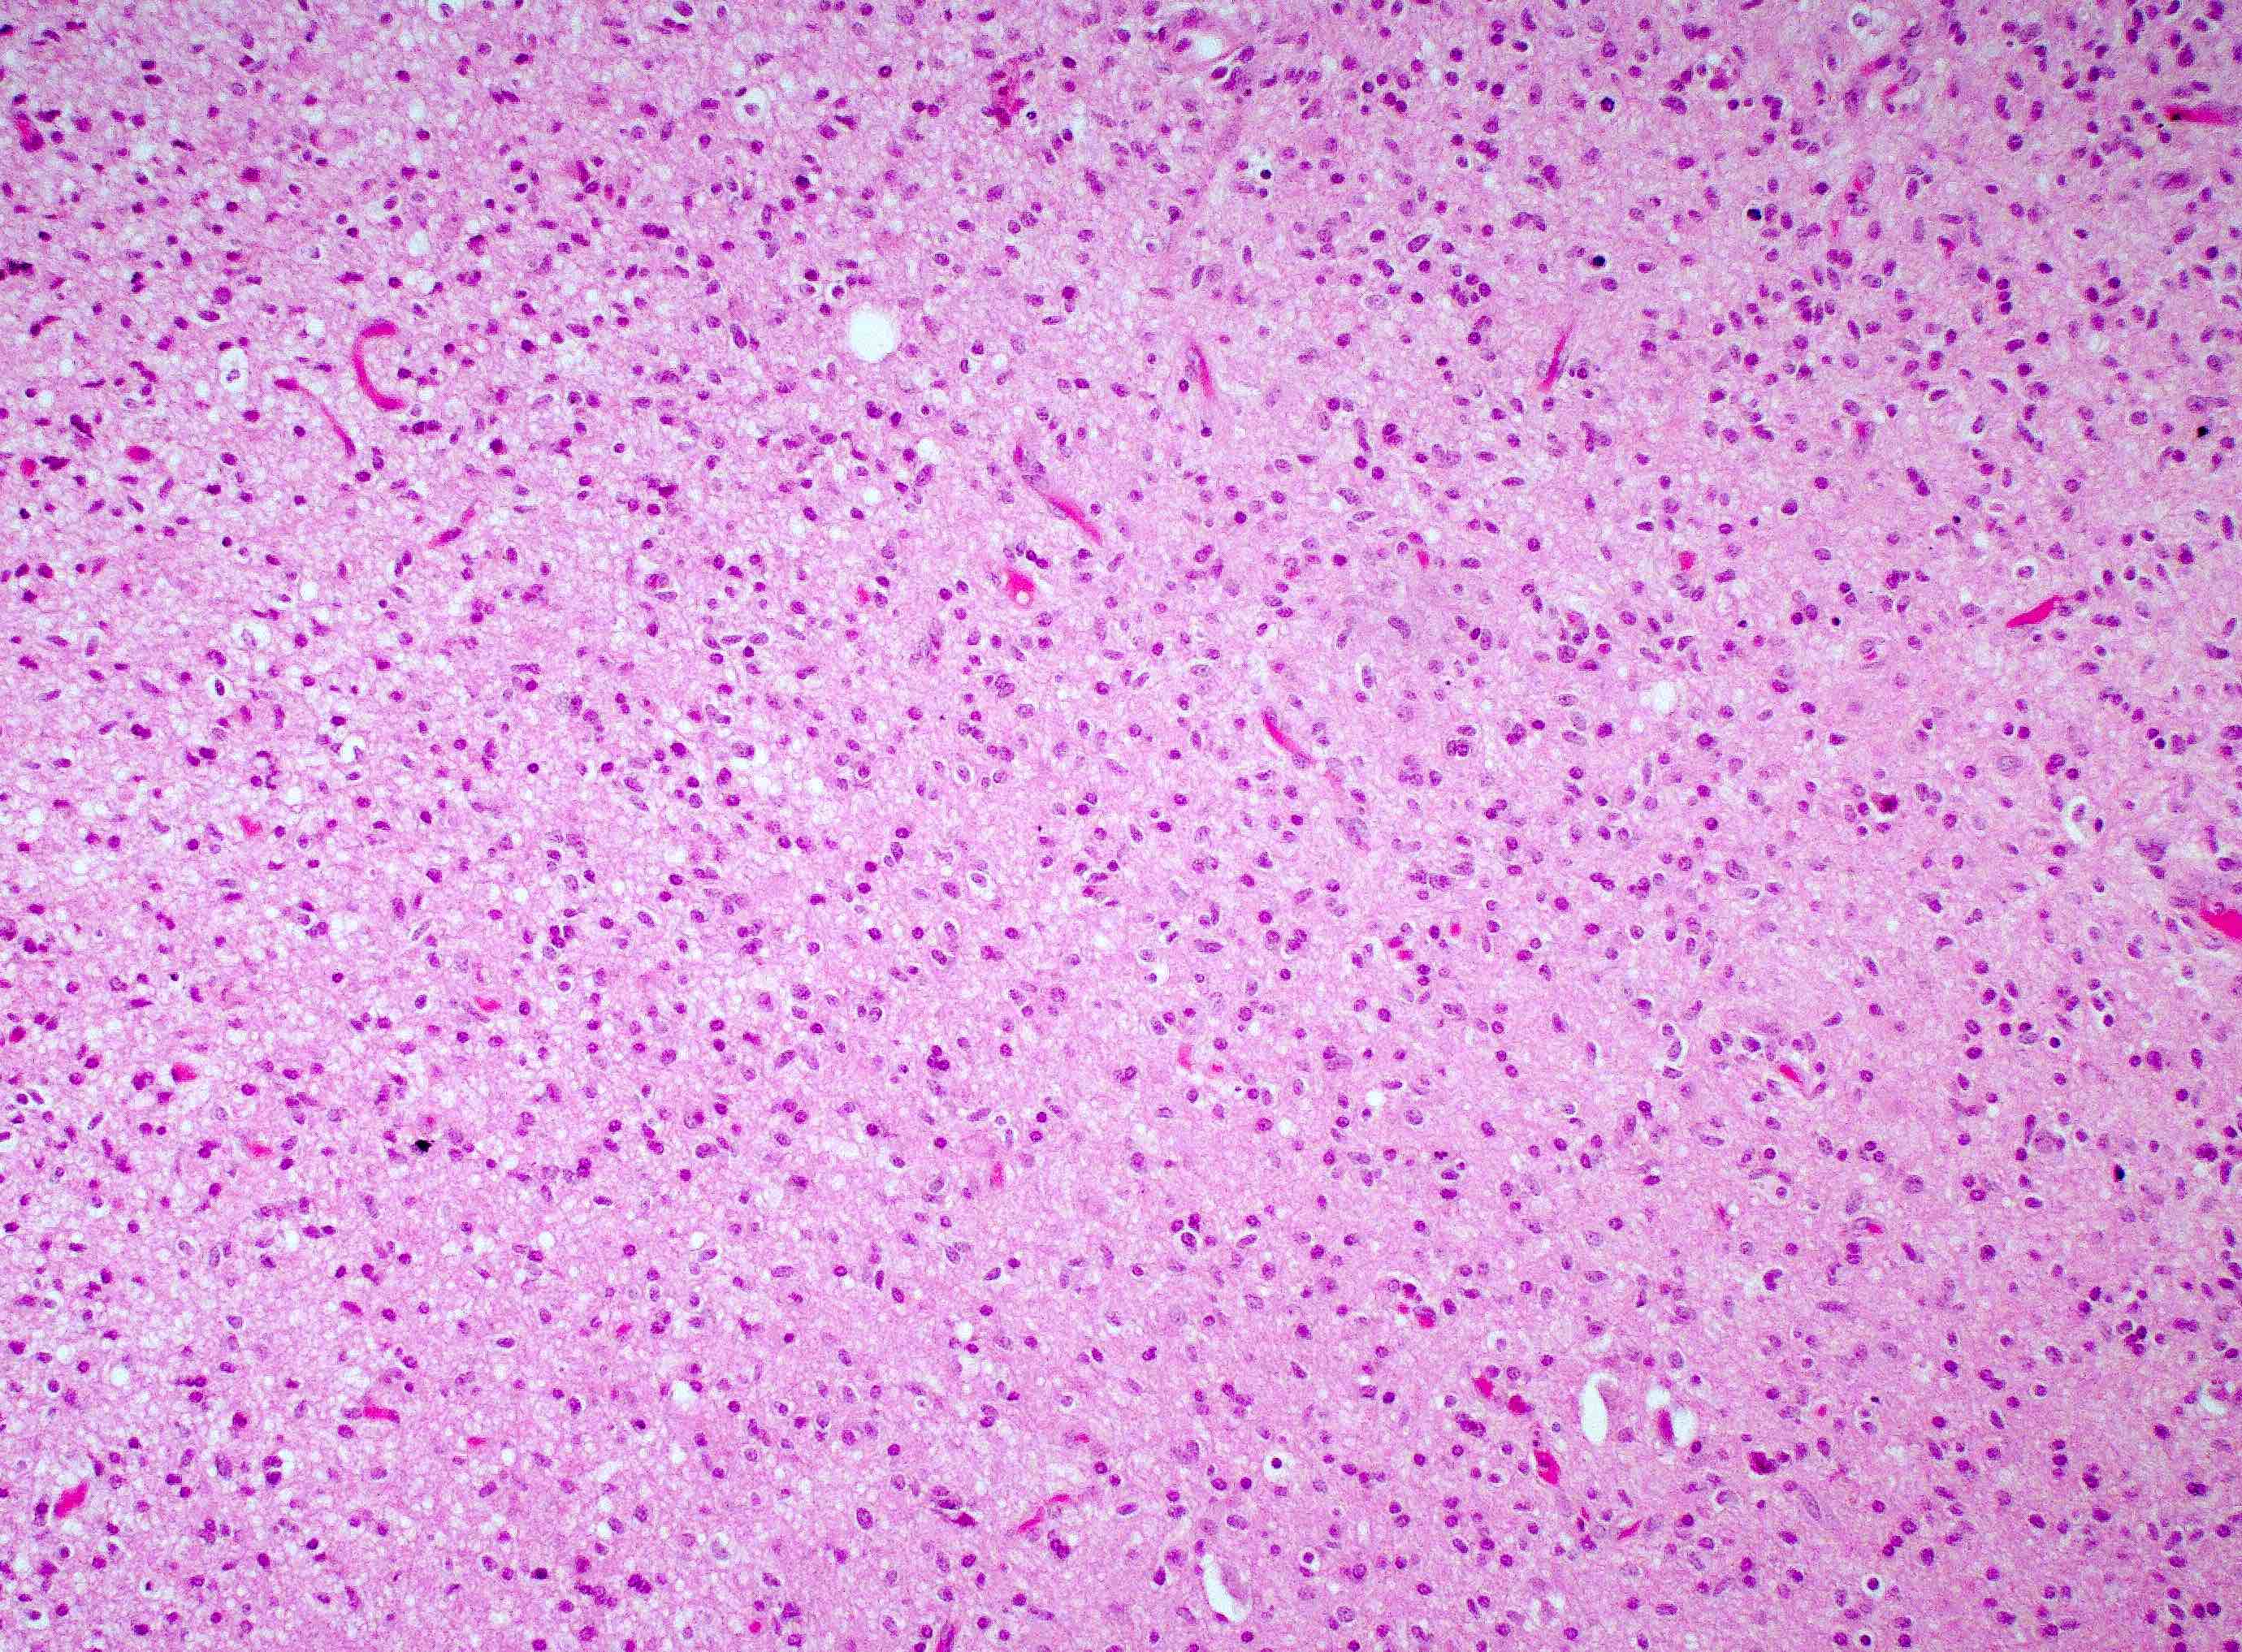

Microscopic (histologic) description

- Infiltrating, hypercellular astrocytic neoplasm often with hyperchromatic, elongated nuclei and irregular nuclear membranes

- Typically mitotically active, though not required if molecular criteria are met

- Microvascular proliferation or necrosis is required for a histologic diagnosis of GBM

- Microvascular proliferation: multilayered, small caliber vessels with glomeruloid appearance (J Neuropathol Exp Neurol 1992;51:488)

- Necrosis: can be geographic or pseudopalisading with neoplastic cells surrounding central necrosis

- Greater association of thrombosis and necrosis in IDH wild type GBM than in IDH mutant grade 4 astrocytomas (Acta Neuropathol 2016;132:917)

- Variable cell morphology: undifferentiated / primitive neuronal cells, astrocytic, gemistocytic, oligodendroglial-like, small cell, lipidized, granular, epithelioid, giant cells, mesenchymal metaplasia and epithelial metaplasia

Microscopic (histologic) images

Contributed by Bharat Ramlal, M.D. and Meaghan Morris, M.D., Ph.D.